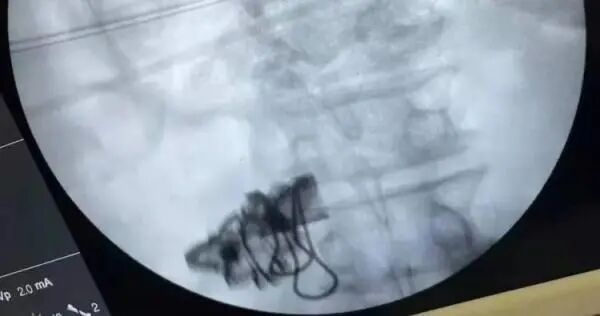

原来,近日沈先生在外和人发生口角,大吵一架,回家后越想越气,一怒之下扯下衣服上的蝴蝶状金属装饰片塞进了嘴里,硬生生吞了下去。等气头过了,肚子开始疼了,理智才回来,沈先生一路捂着肚子来到萧山区第一人民医院急诊科寻求帮助。

吞入异物极容易造成咽喉、食道、胃肠道以及腹腔内血管、脏器等的损伤。急诊医生马上联系了胃肠外科的陈强医生进行会诊,通过拍片、CT检查,明确沈先生的病情。

- 人一冲动就会做傻事!比如下面这位沈先生和人吵架后越想越气,竟把金属装饰片吞入肚中!这下事情严重了!原来,近日沈先生在外和人发生口角,大吵一架,回家后越想越气,一怒之下扯下衣服上的蝴蝶状金属装饰片塞...